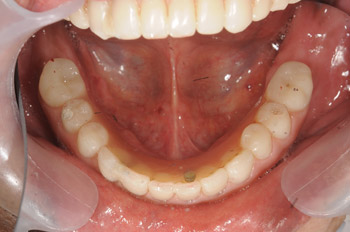

叢生の方の歯列矯正と補綴による治療

元スタッフの歯列矯正とセラミック補綴による叢生の治療

入社前に試みた美容歯科治療が予後不良であることがわかり、やり替えが必要な状態でした。見た目を良くする治療により咬み合わせがおかしくなり、再治療を希望しました。歯科での知識を身に着けたことにより、不良補綴のみならず全体的な治療を望むようになりました。

Before

不正咬合の種類としては、叢生という歯がガタガタに並んだ状態でした。この歯並びを強引に補綴(被せ物)の向きによって変えようとしたことで、全体的な咬み合わせのバランスがおかしくなってしまったようです。きちんと矯正にて歯の根から動かし、正しい咬み合わせを作っていきました。

After

歯並びがしっかりと整いましたので不良補綴物のやり替えを行なっていきました。本人の希望でかなり白い色味に合わせていきました。天然歯を定期的にホワイトニングで調整する必要はありますが、白い歯を好まれる方にはこのような色味にすることも可能です。

Process

すべてのセラミック矯正が悪いとは思いませんが、咬み合わせを考えないセラミック矯正は、彼女のように痛みや予後不良を起こす原因となることがあります。そのため、当院では特別な場合を除き、セラミックによる歯並び矯正は行っておりません。期間や費用は多少かかりますが、残りの人生の中で自分の歯を美しく健康に長く保つためには、歯列矯正の方が有効であることが多くあります。当院では、セラミック矯正のリペア治療も承っています。セラミック矯正をしたものの、咬み合わせがおかしくなったと感じたら、お早めにご相談下さい。

治療の内容 マルチブラケット(クリア)による歯列矯正とセラミック補綴による総合治療。

期間・回数 3年7ヶ月・28回(カウンセリング・検査含む)

費用 自由診療:マルチブラケット(クリア)+セラミッククラウン✕4歯+セラミックインレー✕1歯+ゴールドインレー✕1歯 総額 1,326,000円(税込1,458,600円)(調整料28回分含む)